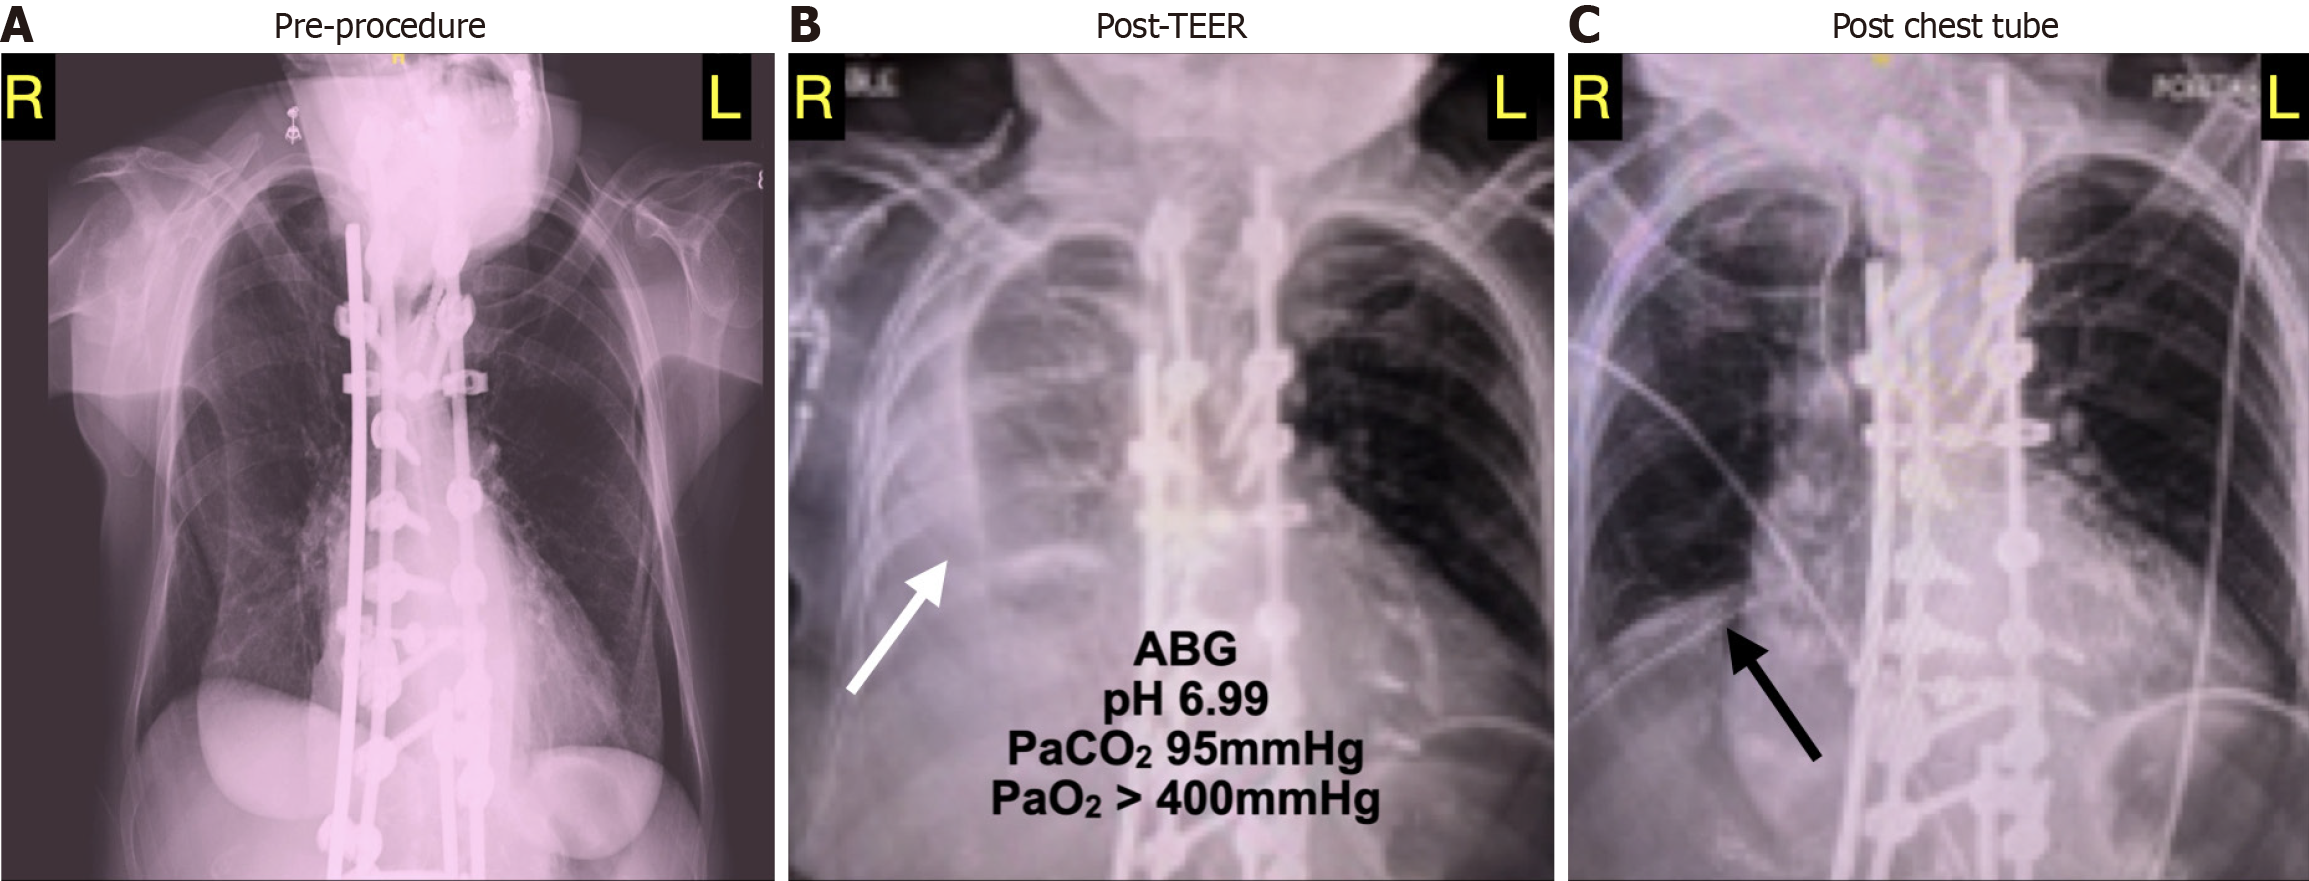

Figure 2 Chest X-ray.

A: Pre-procedure chest radiograph obtained the day before the scheduled mitral clip procedure. The lung fields appear hyperinflated with flattened diaphragms. There is extensive hardware (rods) seen along the spine; B: Post-procedure chest radiograph showing new haziness (white arrow) consistent with fluid. At this time, the patient was hypotensive and severely acidotic most due to a respiratory acidosis presumably related to extensive right lung collapse; C: Post-chest-tube-placement chest radiograph showing clearance of right pleural fluid. The lung fields appear smaller perhaps consistent with pulmonary atelectasis. As the prior films also see, there is extensive hardware along the spine.